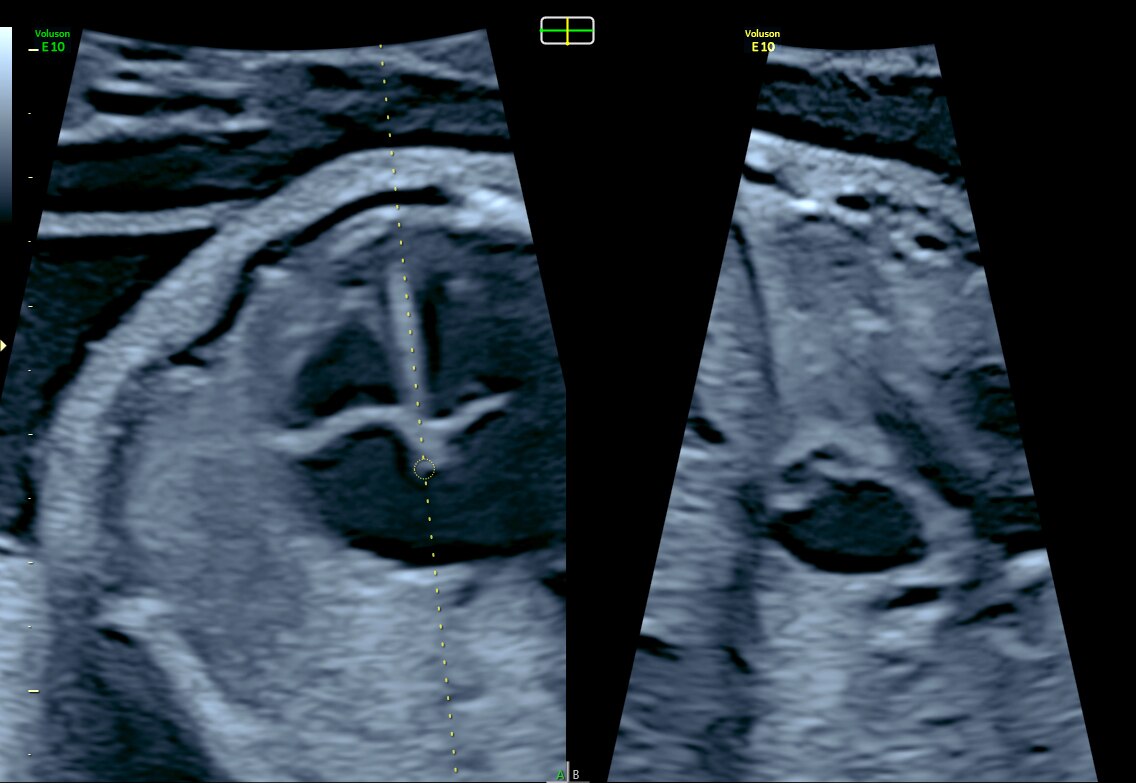

3VV and LVOT with Radiantflow™ in Dual Display